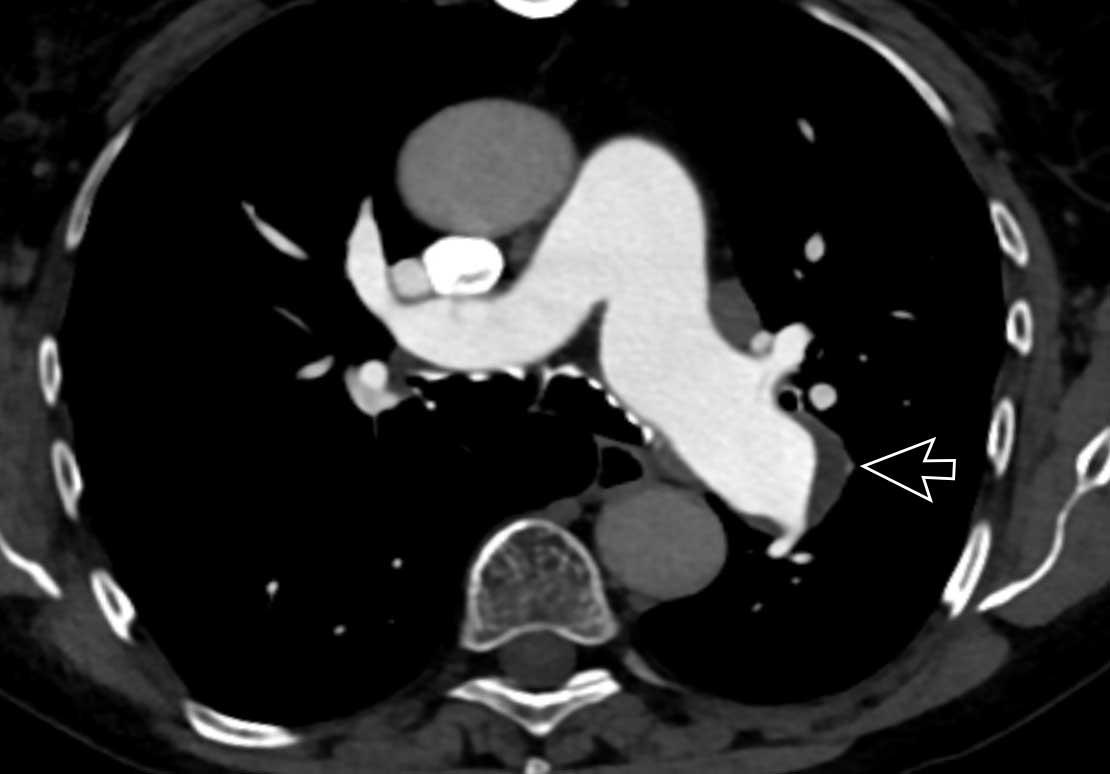

Đây là các hình ảnh của bệnh nhân nữ 59 tuổi tại khoa cấp cứu,

minh họa rõ ràng các huyết khối ở các mức độ khác nhau.

Cuộn qua các hình ảnh.

- Huyết khối trong động mạch thùy đến thùy trên phổi phải.

- Huyết khối tại lỗ vào của động mạch phân thùy đáy sau của thùy dưới phổi phải.

- Huyết khối dưới phân thùy ở phân thùy đáy trước của thùy dưới phổi phải, vài nhánh phía sau động mạch phân thùy.

- Huyết khối tại chỗ phân đôi phân thùy của thùy trên phổi trái.

- Huyết khối tiếp tục lan về phía ngoại vi trong động mạch dưới phân thùy.